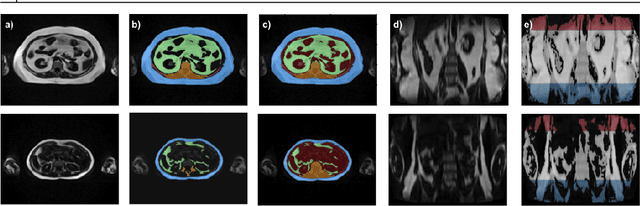

Abstract:Purpose: Development of a fast and fully automated deep learning pipeline (FatSegNet) to accurately identify, segment, and quantify abdominal adipose tissue on Dixon MRI from the Rhineland Study - a large prospective population-based study. Method: FatSegNet is composed of three stages: (i) consistent localization of the abdominal region using two 2D-Competitive Dense Fully Convolutional Networks (CDFNet), (ii) segmentation of adipose tissue on three views by independent CDFNets, and (iii) view aggregation. FatSegNet is trained with 33 manually annotated subjects, and validated by: 1) comparison of segmentation accuracy against a testingset covering a wide range of body mass index (BMI), 2) test-retest reliability, and 3) robustness in a large cohort study. Results: The CDFNet demonstrates increased robustness compared to traditional deep learning networks. FatSegNet dice score outperforms manual raters on the abdominal visceral adipose tissue (VAT, 0.828 vs. 0.788), and produces comparable results on subcutaneous adipose tissue (SAT, 0.973 vs. 0.982). The pipeline has very small test-retest absolute percentage difference and excellent agreement between scan sessions (VAT: APD = 2.957%, ICC=0.998 and SAT: APD= 3.254%, ICC=0.996). Conclusion: FatSegNet can reliably analyze a 3D Dixon MRI in1 min. It generalizes well to different body shapes, sensitively replicates known VAT and SAT volume effects in a large cohort study, and permits localized analysis of fat compartments.